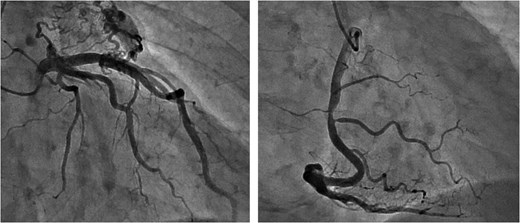

Following closure of the PA and cessation of cardiopulmonary bypass, ST-segment elevation was observed, accompanied by a deterioration in the patient's hemodynamics. Consequently, an intra-aortic balloon pump (IABP) was inserted via the right femoral artery and coronary angiography (CAG) revealed spasms along the entire length of the RCA and obtuse marginal artery (Fig. 5). These spasms improved generally after administration of nitroglycerin (Fig. 6). However, ventricular fibrillation was provoked, leading to unstable hemodynamics. Therefore, veno-arterial extracorporeal membrane oxygenation was initiated, and the surgery was concluded. Extracorporeal membrane oxygenation (ECMO) and IABP were withdrawn 4 days and 5 days after surgery, respectively. The patient's postoperative course was good, and he left the hospital on post-operative day 20.

Intraoperative CAG revealing vasospasms along the entire length of the RCA and OM artery.